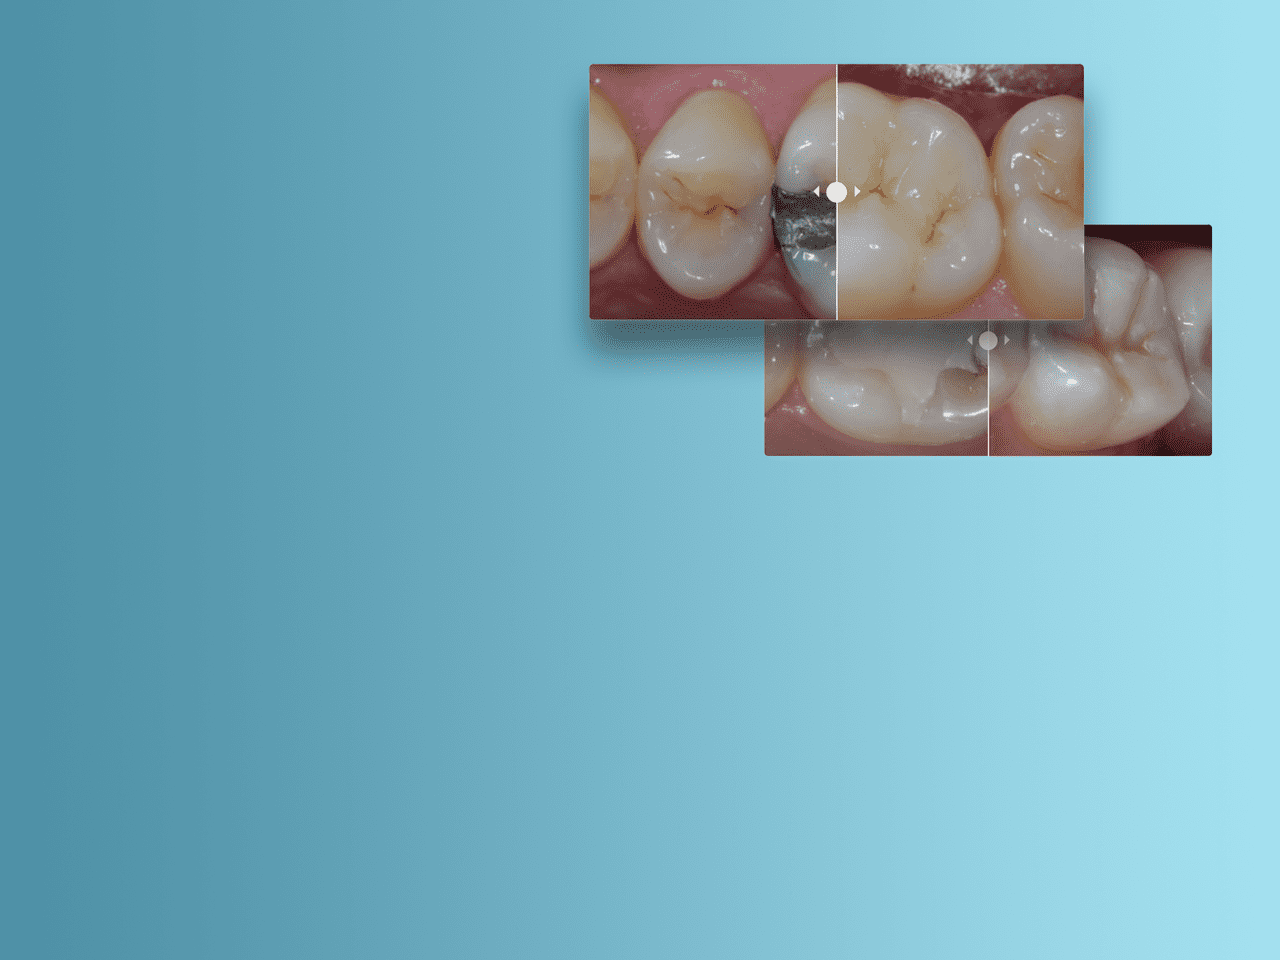

O material SDR flow+ é uma inovação única na medicina dentária - um bulk fill fluido que combina propriedades exclusivas autonivelantes e o melhor stress de encolhimento da categoria - que permite a colocação até 4 mm com excelente adaptação da cavidade, permitindo a colocação de restaurações sem falhas.

Casos clínicos de Classe II

Como parte da sua abordagem de Classe II, a Dentsply Sirona fornece as ferramentas e técnicas necessárias para a satisfação do paciente e o sucesso do procedimento.